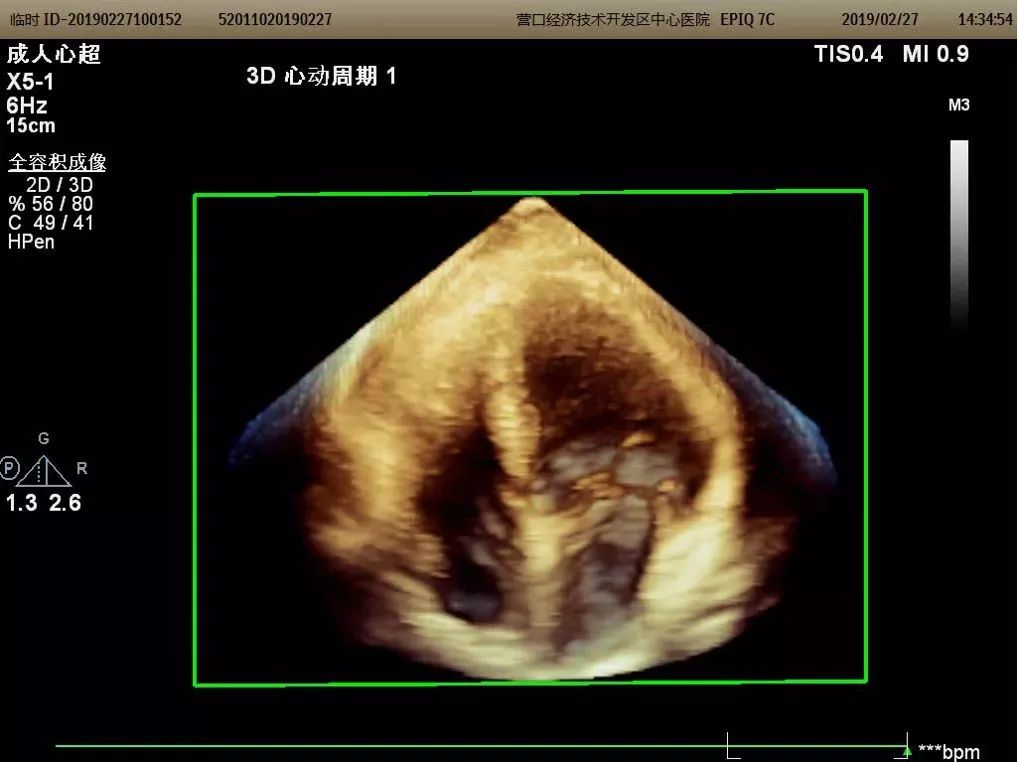

心脏三维超声成像

能够整体、直观的获得心脏内部结构图像,医生可多角度、多切面观察,适用于瓣膜病、先天性心脏病等疾病,使超声诊断更加准确。

三维成像